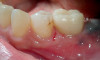

To avoid potential soft tissue collapse when the impression was captured, a custom impression abutment was created to support the soft tissue and properly communicate to the laboratory technician what had developed intraorally (Figure 10). This technique may be used with either open-tray or closed-tray impression abutments. The impression was taken and the custom healing abutment was reinserted intraorally while the laboratory constructed the restoration. The completed restoration was returned, the custom healing abutment was removed, and the implant restoration was inserted. The result was an emergence profile that mimicked a natural molar, enabling natural-looking esthetics (Figure 11). A radiograph demonstrated a smooth transition emanating from the implant platform to support an emergence profile that allowed soft-tissue maintenance and helped to eliminate potential food traps (Figure 12).

Fig 12. Radiograph of the final restoration demonstrating a natural emergence profile of the tooth that was replaced.

Figure 12